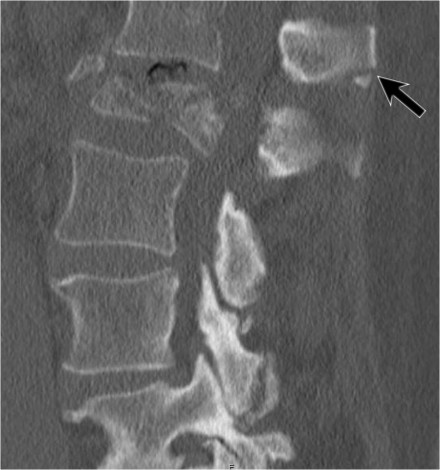

Sternum fracture

The image shows a vertebral fracture with a transverse fracture of the spinous process, but also a fracture of the sternum.

Analogous to the 3-column classification of Denis, some investigators

consider the sternum as the fourth column in upper thoracic spinal

fractures and recognize it as an independent variable in the assessment

and treatment of these patients (5).